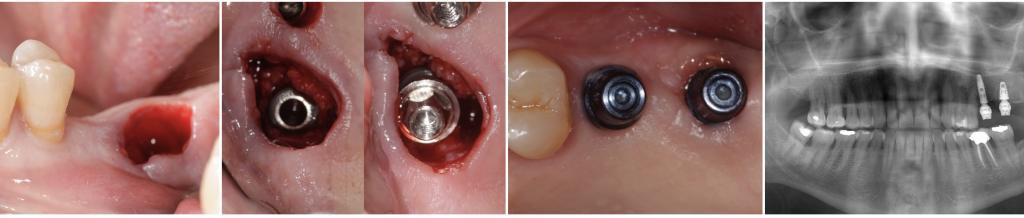

Fig.3- Immediate implant (Alvim, Neodent®) with the definitive Micro-abutment placed the same day of the surgery.

The CM connection has a virtual absence of microgap and, therefore, of micro-movements (Weng 2011). It allows bone overgrowth beyond the implant platform (Degidi 2008, Weng 2011).

Linkevicius et al., suggested that dimensional bone changes occurred during biologic width formation, considering the soft-tissue thickness as a key parameter and not just the platform switching (Linkevicius 2010). Degidi et al. introduced the definitive abutment at the same time of the implantation (Degidi 2013). We screwed to the implant the definitive abutment to help to preserve the initial biologic the same day of the implant surgery with favorable results.

The tapered implant design, with switching platform, had less bone resorption compared with traditional matching implants.16 We used four dental implants (Alvim CM, Neodent) with a tapered design, switching platform, cone morse connection and unpolished surface to get bone over the implant platform leaving the implant placement 2 mm subcrestal. Chu et al. reported that subcrestal placement decreased the peak of compressive stress at the crestal cortical bone and transferred it toward the trabecular bone (Chu 2011).